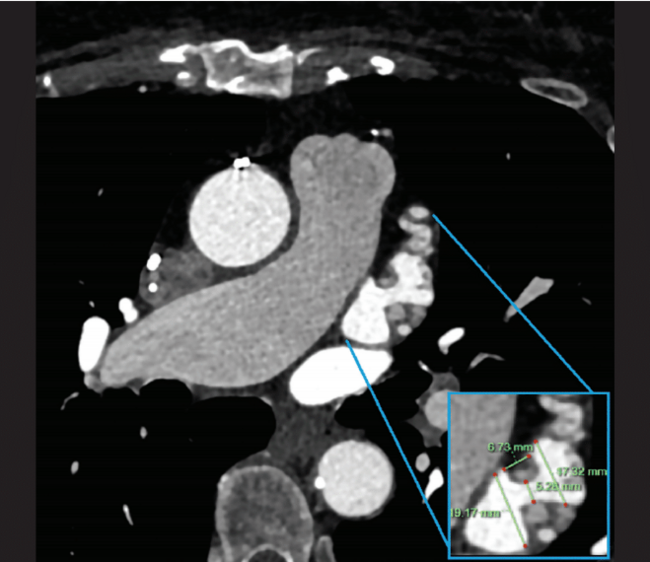

A 78-year-old woman was referred to Northside Hospital Heart Institute for possible LAAC. She had a history of coronary artery bypass grafting (CABG) over 5 years ago, permanent AF with history of atrioventricular node ablation, and permanent pacemaker implantation. Her CHA2DS2-VASc score was 5 due to hypertension, age >75, diabetes, and vascular disease. This placed her at high risk for stroke, but her cardiologist deemed her not to be a good candidate for long-term oral anticoagulation due to intracranial hemorrhage with multiple falls. An operative report of the CABG was obtained, but the report showed only 3-vessel bypass with no report of LAA ligation. Computed tomography (CT) with contrast of the heart was also obtained, which is standard practice for many of our LAAC procedures, especially for patients who have had prior cardiac surgeries. There was a 5.3-mm leak noted at the surgical closure at the base of the LAA (Figure 1). This leak was too large to close with endovascular coils, and there was concern about using an endovascular plug due to length of the leak and possible effects of radial forces over time in the channel. The Amplatzer Amulet device was chosen for this case, with the plan to place the lobe inside the LAA and place the disc covering the channel with forces after closure to be axial in direction. The procedure was performed under general anesthesia and transesophageal echocardiography (TEE) imaging. LAAC procedures at Northside Hospital Heart Institute are usually performed using TEE guidance only, with no use of contrast, since our noninvasive physicians (Drs John Ricketts and Colin O’Brian) provide imaging for transseptal puncture, device deployment, and post-imaging for any leaks, including 3D TEE at every step when needed. Due to the unusual nature of this anatomy, we performed contrast fluoroscopy of the LAA. Figures 2A and 2B show the pre-implant and periprocedural TEE images. Figure 3 shows the contrast injection through the 12 French Torque Vue 45-degree Amulet delivery sheath (Abbott) and the Glidewire (Terumo Interventional Systems) in the LAA. The placement was primarily guided by TEE imaging. The smallest size (16 mm) Amulet device was chosen for closure. Figure 4 demonstrates placement under fluoroscopy. Figures 5A and 5B demonstrate closure using TEE imaging. Post procedure, the patient was placed on aspirin and clopidogrel for 3 months. Once adequate seal is confirmed at 3 months, the goal is for the patient to switch to aspirin (81 mg).